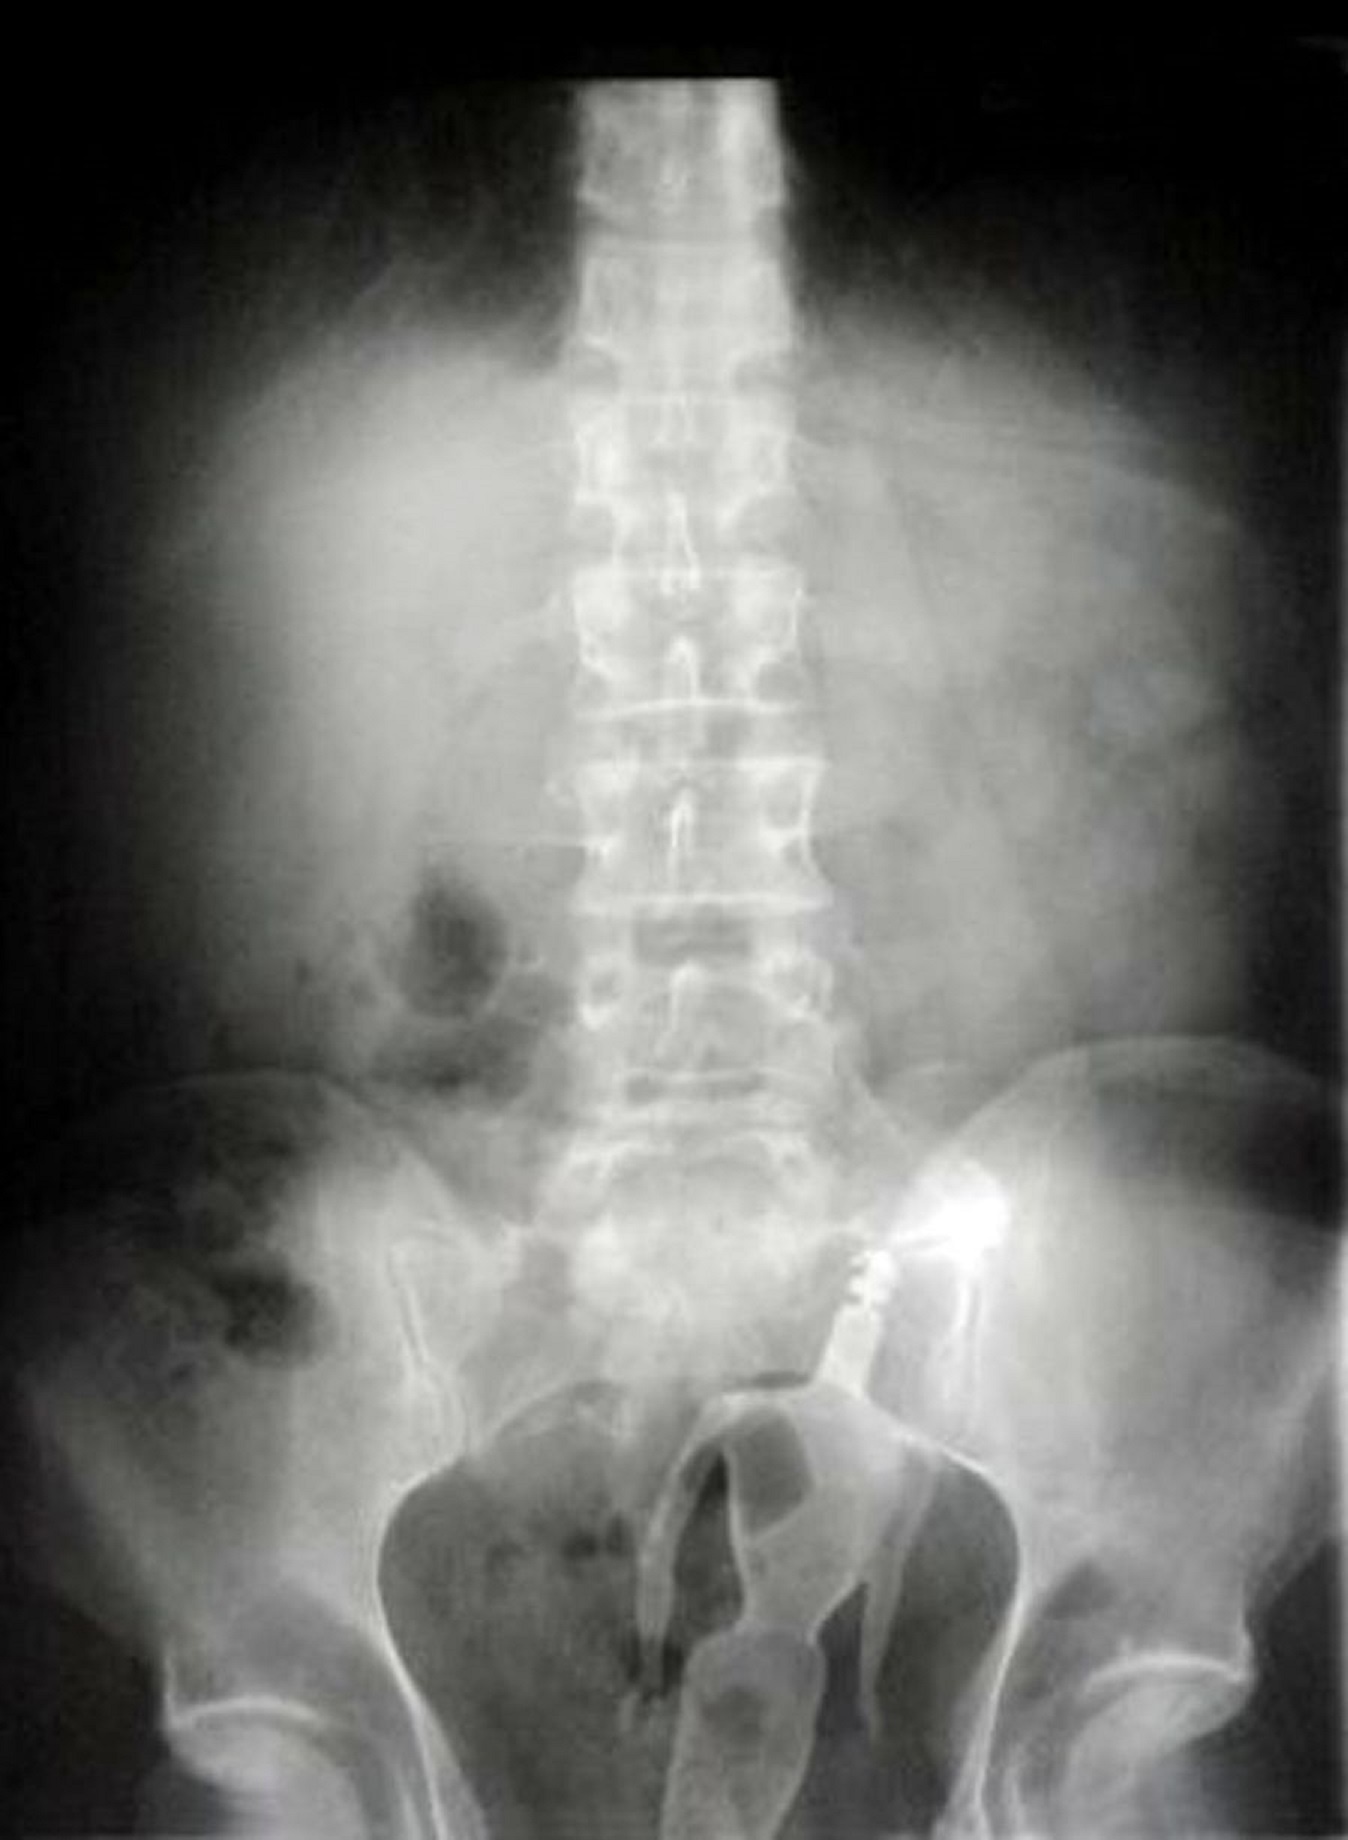

| Một người đàn ông 60 tuổi ở thành phố Chu Hải, tỉnh Quảng Đông, Trung Quốc, đến bệnh viện vì nghĩ ông mắc chứng táo bón. Tuy nhiên, hình ảnh X-quang cho thấy một cái chai đang kẹt trong hậu môn bệnh nhân. |

| Bình khử mùi nằm trong trực tràng một bệnh nhân trong suốt một bữa tiệc. |